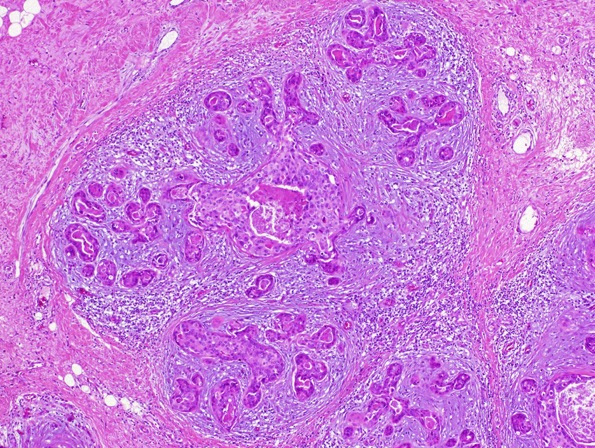

Teníamos 3 temas específicos de AP (célula, tejido y neoplasias) en las que se dan generalidades que vi en 3º de carrera y de las que suelen preguntar poco y luego un repaso de la anatomía patológica de las distintas patologías que hemos ido viendo en el resto de asignaturas.

El manual, es el que menos me ha gustado hasta la fecha. Para empezar, era en blanco y negro, como la mayoría, algo que dificulta mucho estudiar AP, en donde las tinciones son una parte fundamental. Había numerosas imágenes con pies de página explicando bastante bien lo que se veía  en la imagen, pero lamentablemente no he podido sacarle todo el jugo que me gustaría (afortunadamente para los siguientes estudiantes, a partir del año que viene todos los manuales son en color, así que no tendrán ese problema). Otro aspecto que no me ha gustado es que lo he visto un poco cojo en cuanto a contenido en algunas partes... De hecho, hay bastantes patologías que no se han visto (pero que quedan perfectamente cubiertas por el resto de manuales) y me he sorprendido echando de menos que aparecieran en el manual e incluso sabiendo la AP de las patologías que no estaban... Supongo que "el recorte" se debe más que nada a factor tiempo: solo hay un día de estudio, es una asignatura sobre todo de repaso y con 100 páginas de AP es suficiente...